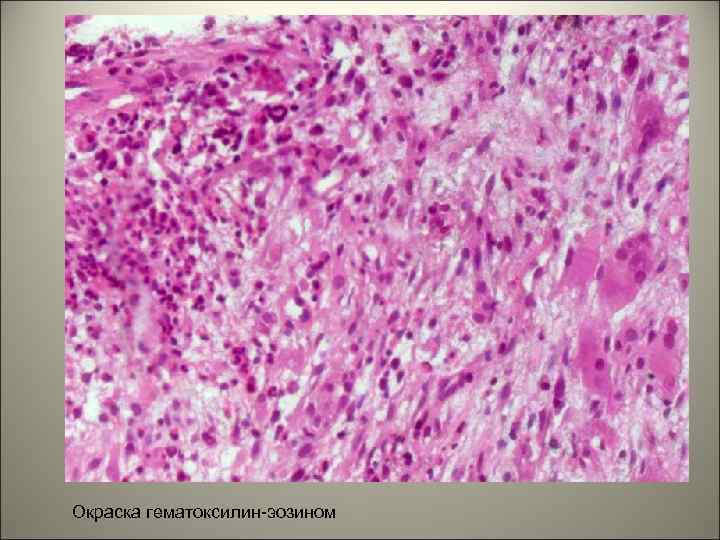

• При гистологическом исследовании выявлена опухоль, которая состоит из полиморфного клеточного инфильтрата с одноядерными и многоядерными (атипичными) гистиоцитами (клетками Лангерганса), эозинофилов, гранулоцитов и лимфоцитов.

Окраска гематоксилин-эозином

• Смешанный инфильтрат гистиоцитов, эозинофилов и наличие фагоцитов может напоминать – реактивный гистиоцитоз, лимфому Ходжкина и синусный гистиоцитоз с выраженной лимфаденопатией (болезнь Росаи Дофмана). • При ЛКГ – клетки позитивны на S 100 и CD 1 a. • При узловатой форме ЛКГ- необходима диагностика с фолликулярной саркомой из дендритных клеток.

• Для уточнения диагноза проведено иммуногистохимическое исследование с маркерами пролиферативной активности - Ki 67, маркером гистиоцитов CD 68, маркерами клеток Лангерганса CD 1 a и S 100.